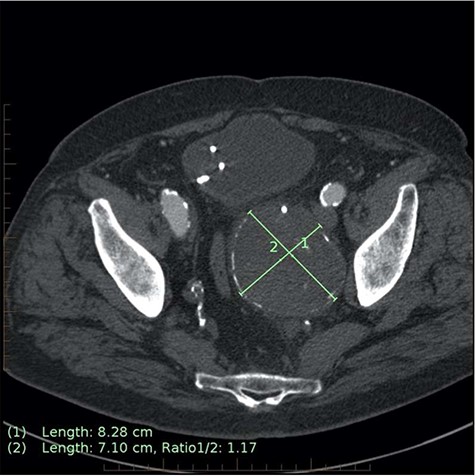

After relocating to the catchment area of our hospital, he presented in acute urinary retention. A CT kidney, ureters and bladder (CTKUB) demonstrated left hydronephrosis and hydroureter secondary to extrinsic compression from the enlarged left IIAA (from 58 mm to 76 mm in diameter) (Fig. 1A and B). Embolization was delayed by the associated acute kidney injury, which was first managed by the urologists with J-J stent insertion for ureteric decompression. He then entered a period of repeated urological interventions due to complications from his ureteric instrumentation, including urosepsis requiring a prolonged intensive care unit admission. When his urinary tract infections had cleared, a CTA demonstrated the IIAA to have further increased (83 mm × 71 mm), prompting urgent embolization (Fig. 2).

Axial CT image on 6-month follow-up demonstrating expansion of the IIAA by 7 mm, now measuring 83 × 71 mm axially (previously 76 × 62 mm).